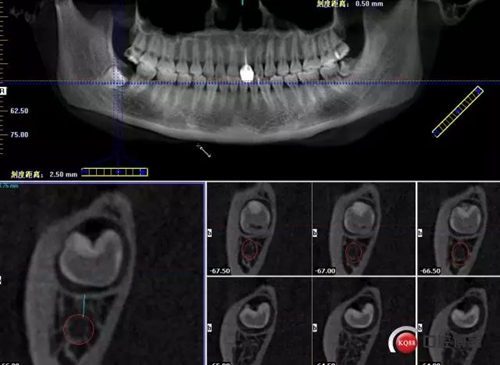

1498615723_447506.png

牙齒上1/3CT切片,神經(jīng)管在下方